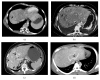

Splanchnic vein thrombosis (SVT) is a broad term that includes Budd-Chiari syndrome and occlusion of veins that constitute the portal venous system. Due to the common risk factors involved in the pathogenesis of these clinically distinct disorders, concurrent involvement of two different regions is quite common. In acute and subacute SVT, the symptoms may overlap with a variety of other abdominal emergencies while in chronic SVT, the extent of portal hypertension and its attendant complications determine the clinical course. As a result, clinical diagnosis is often difficult and is frequently reliant on imaging. Tremendous improvements in vascular imaging in recent years have ensured that this once rare entity is being increasingly detected. Treatment of acute SVT requires immediate anticoagulation. Transcatheter thrombolysis or transjugular intrahepatic portosystemic shunt is used in the event of clinical deterioration. In cases with peritonitis, immediate laparotomy and bowel resection may be required for irreversible bowel ischemia. In chronic SVT, the underlying cause should be identified and treated. The imaging manifestations of the clinical syndromes resulting from SVT are comprehensively discussed here along with a brief review of the relevant clinical features and therapeutic approach.